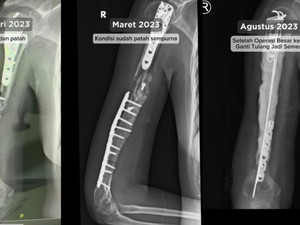

Kondisi Terkini Hani usai Menjalani Perawatan

Sampai saat ini Hani masih menjalani perawatan intensif. Namun kanker tulang yang dialaminya itu sudah dinyatakan remisi oleh dokter.

"Kalau misalnya untuk lukanya, sampai saat ini masih ada infeksi. Kalau misalnya ditargetkan berapa minggu ke depan hasil darahnya kurang baik, dan masih terinfeksi, harus dilakukan operasi kecil untuk mengatasi infeksinya," ucap Hani.

Ia juga mengaku sudah bisa menggerakan tangannya, sehingga bisa menjalani aktivitas sehari-hari.

"Alhamdulillah untuk saat ini tangan saya nggak bisa geraknya itu dari sikut sampai ke bahu. Dari pergelangan tangan sampai jari-jari normal," imbuhnya.